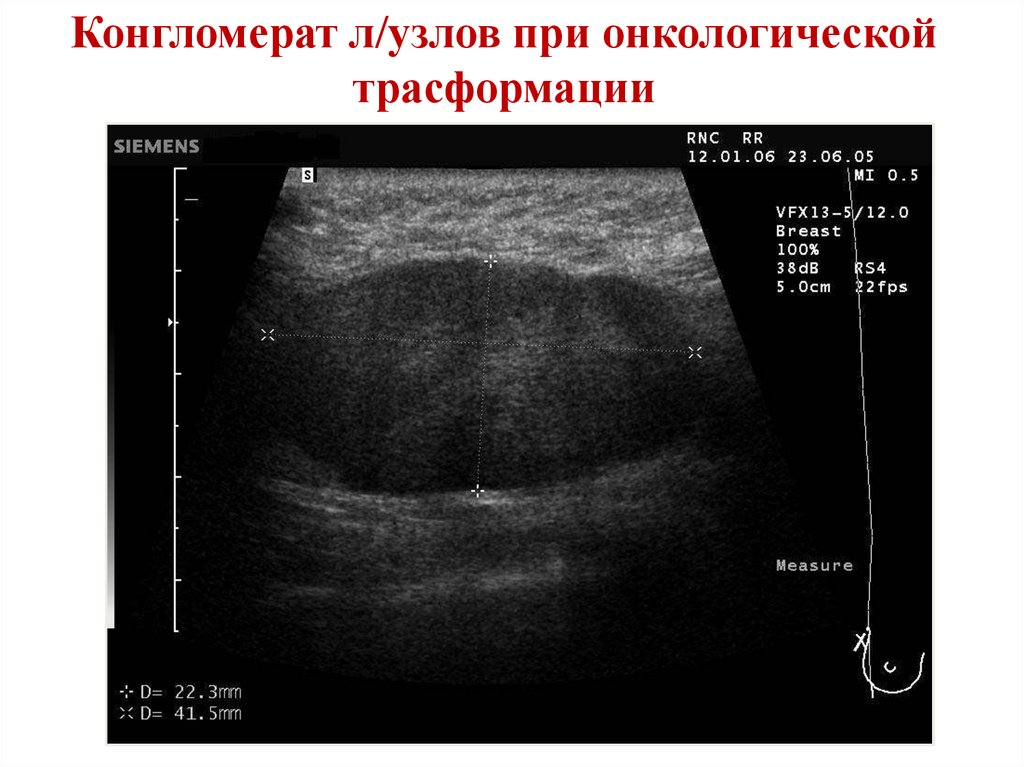

Конгломерат л/узлов при онкологической

трасформации